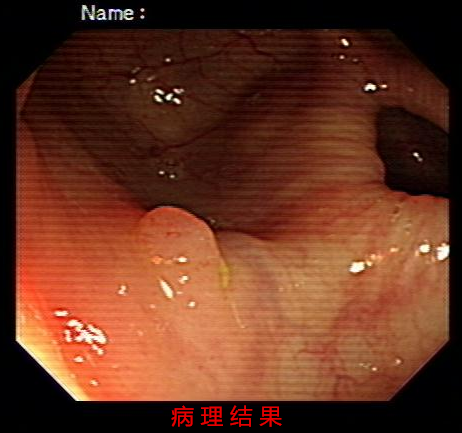

����Ϊ�˽��ʹ��������Ӱ�죬���ݶ���س�ҽԺ����������С��̽��8�������ͳ������ˣ�ͻ�ƴ�ͳ�ĸس����ä����120°��ⲻ�����ǣ�5���ӾͿ���ȷ�ﲡ�飬������ֹ������Ϯ!